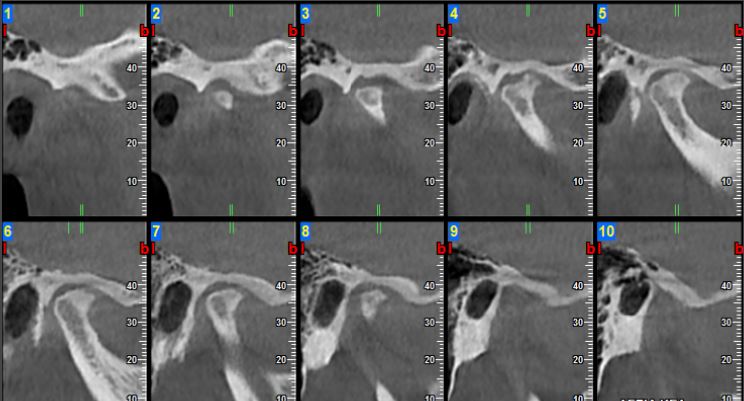

Severe Osteoarthritis of the Right TMJ. Reduced joint space, flattening of the head of the condyle, Cortical erosions and subchondral cystlike erosions, Osteophyte formation and loose bodies (joint mice) within the joint cavity.